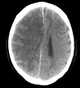

Venous cerebral infarction

Cerebral venous sinus thrombosis (CVST) is the presence of a blood clot in the dural venous sinuses, which drain blood from the brain. Symptoms may include headache, abnormal vision, any of the symptoms of stroke such as weakness of the face and limbs on one side of the body, and seizures. [Source: Wikipedia ]